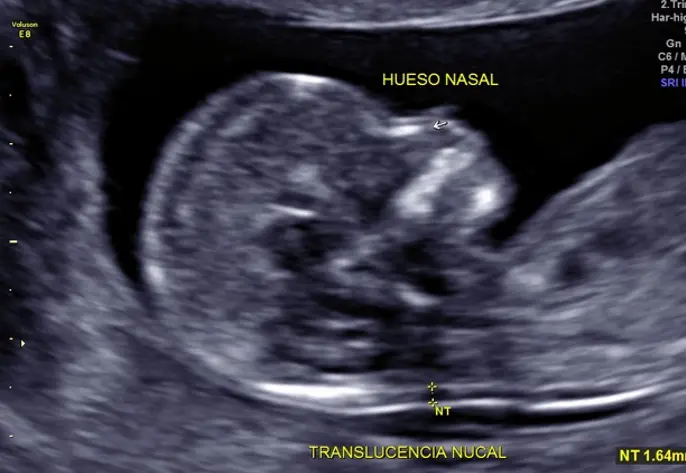

En este estudio de primer trimestre se realiza una evaluación estructural detallada de bebé de cabeza a pies para descartar malformaciones mayores y revisar que todos los órganos vayan desarrollándose de manera normal, también se buscan cuatro marcadores en bebé que son llamados genéticos (translucencia nucal, hueso nasal, ductus venoso y flujo tricuspídeo), se sabe que en bebés sanos estos marcadores están presentes y deben ser normales, los bebés que los tienen alterados tienen mayor riesgo de alteraciones genéticas como síndrome de Down, como parte de este estudio se toma la presión del útero y en combinación con otros datos como peso, presión arterial del brazo, etc se puede calcular el riesgo de preeclampsia (presión alta al final del embarazo).

- Realizar una evaluación estructural temprana detalla para descartar malformaciones mayores.